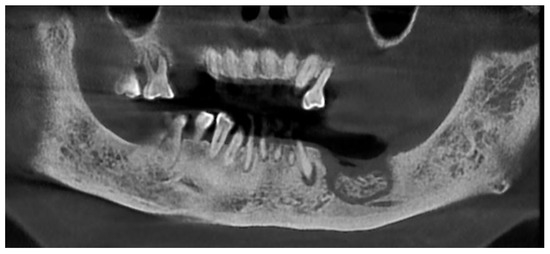

Figure 1.

Radiologic appearance of focal MRONJ lesion in left mandible.

Figure 2.

CBCT showing the necrotic bone extension.